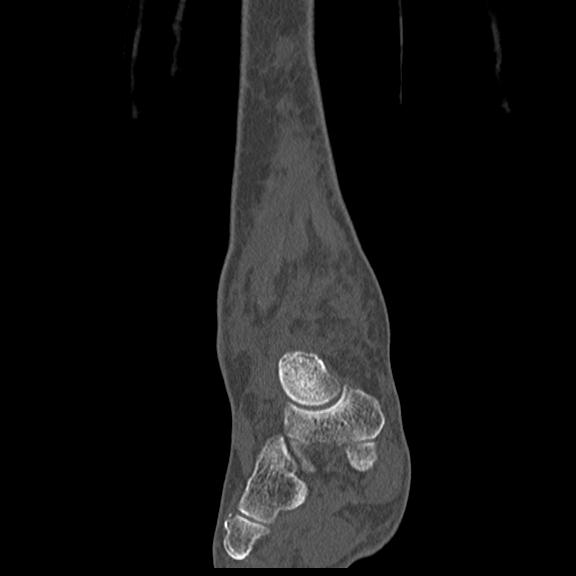

56476 8/28 4R 1/21 2R 左足関節 デジカメ写真 72歳女性 右足関節AS